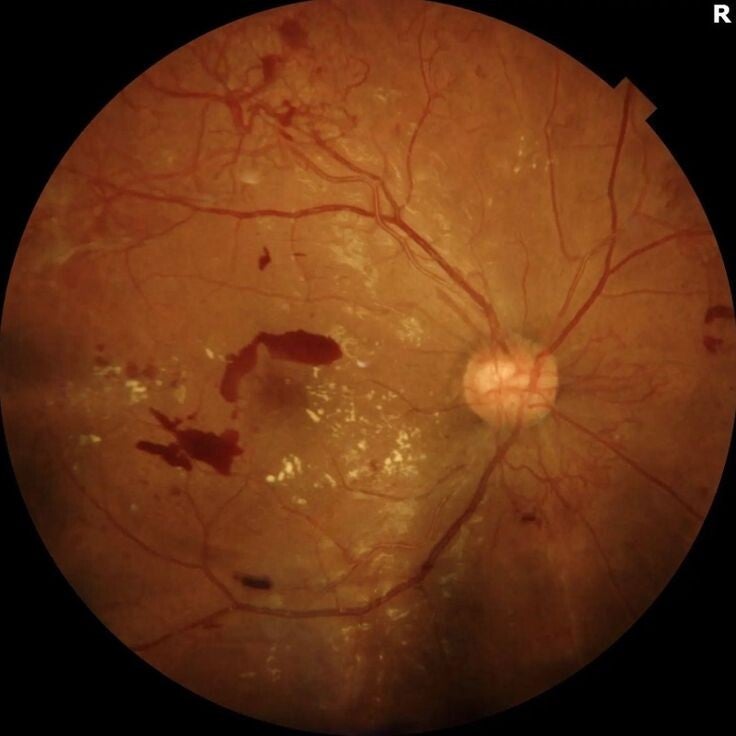

Retinopatía diabética

La mayoría de los pacientes que viven con diabetes desconocen si tienen algún tipo de daño en su retina ya que al inicio de la enfermedad, esta suele no generar síntomas. Una consulta por lo menos una vez al año realizando un estudio conocido como "Fondo de ojo" donde se dilatan las pupilas y se revisa el interior del ojo, puede prevenir daño y ceguera irreversible en estos pacientes. Existen diferentes tratamientos para la Retinopatía diabética dependiendo del estadio en que se encuentre.